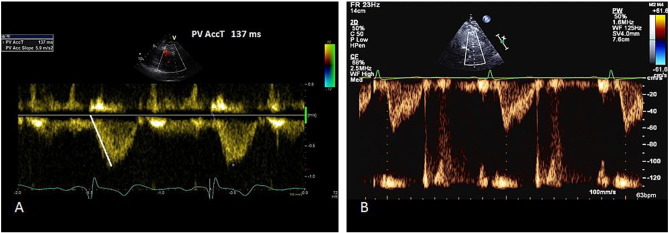

4. Mean pulmonary artery pressure from right ventricular outflow tract (RVOT) acceleration time

Pulse wave of RVOT normally produces a dome shape, but in patients with pulmonary hypertension, there is rapid rise to peak, resulting in shorter acceleration time [17] . A mid-systolic notching could also indicate pulmonary hypertension [17] .

4.1. Method

A pulse wave signal of pulmonic forward flow is obtained at end expiration, just proximal to the pulmonary valve in the parasternal short axis view. The Doppler sample is placed in such a way that the obtained signal has a closing snap but not an opening snap. The quality of the signal is very important and maximum sweep speed must be used to increase accuracy. Furthermore, there should not be spectral broadening.

Right ventricular outflow tract (RVOT) acceleration time is measured from the beginning of the flow to the peak flow velocity (Fig. 4 ). It is important that the marker is placed at the peak first and then tracked back to the onset of flow, as the aim is to measure time taken to peak velocity and not the propagation. A value of > 130 ms is normal, while < 100 ms is highly suggestive of pulmonary hypertension [18] . Mean pulmonary pressure is calculated by the formula: mPAP = 90 − (0.62*ATRVOT ). For example, if the ATRVOT is 80 ms, the mPAP = 90 −(0.62*80), that is 40.4 mmHg (normal < 25 mmHg). On the other hand, if the ATRVOT is 137 ms (as in Fig. 4 ), then the calculated mPAP is 90 −(0.62*137) = 5.06 mmHg.

Fig. 4

Fig. 4.

RVOT acceleration time method for assessing pulmonary pressure.

A—Pulmonary acceleration time measurement.

B—Rapid rise and mid-systolic notching suggesting elevated pulmonary pressure.

4.2. Common pitfalls

Heart rates outside of the normal range (< 60 or > 100 bpm) may reduce the accuracy of this technique. However, when the mean PAP exceeds 25 mmHg, RVOT acceleration time is accurate even in tachycardia [19]  and [20] . More often, the slope of the pulse wave Doppler trace is measured, rather than the time taken from onset to peak velocity. This usually leads to underestimation of the RVOT acceleration time.

7. Right ventricular isovolumic relaxation time (r IVRT)

7.1. Method

TDI is deployed at the lateral tricuspid annulus with a sweep speed of 100 mm/s. Pulse wave (PW) Doppler with a 6 mm sample window is obtained. Right ventricular isovolemic relaxation time (r IVRT) is measured from the offset of the S′ wave to the onset of the E’ wave (Fig. 7 ). r IVRT of > 75 ms reliably predicts pulmonary hypertension while an r IVRT of < 40 ms has a high negative predictive value for pulmonary hypertension [25]  and [26] .

Fig. 7

Fig. 7.

Right ventricular isovolemic relaxation time measurement.